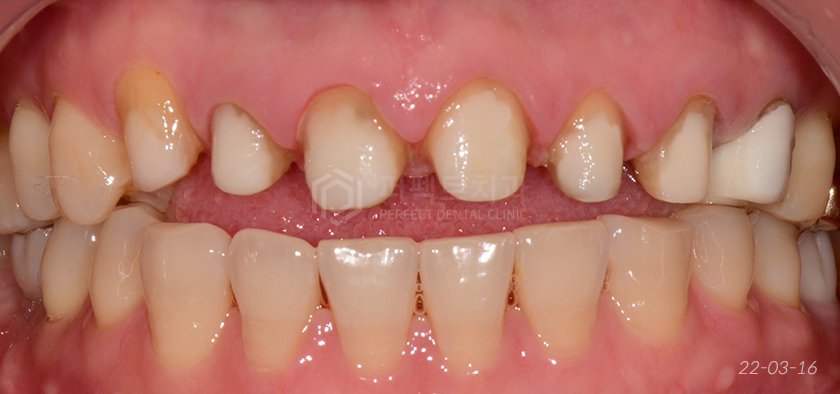

앞니 재치료 후

환자분이 원하시는 대로 아주 자연스럽게 잘 나왔습니다. 발치해야하는 치아가 있다고 말씀드렸었는데

사진 촬영일 기준 오른쪽 작은어금니는 발치 후 임플란트를 식립하는 중이었습니다.

전, 후 비교해봤을 때 보다 가지런하고 좀 더 밝은 치아가 만들어졌습니다.